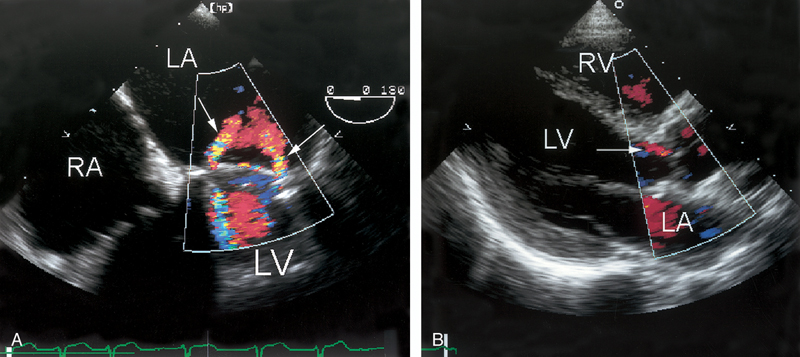

فحوصات تشخيصية لبعض امراض القلب والشرايين التاجية